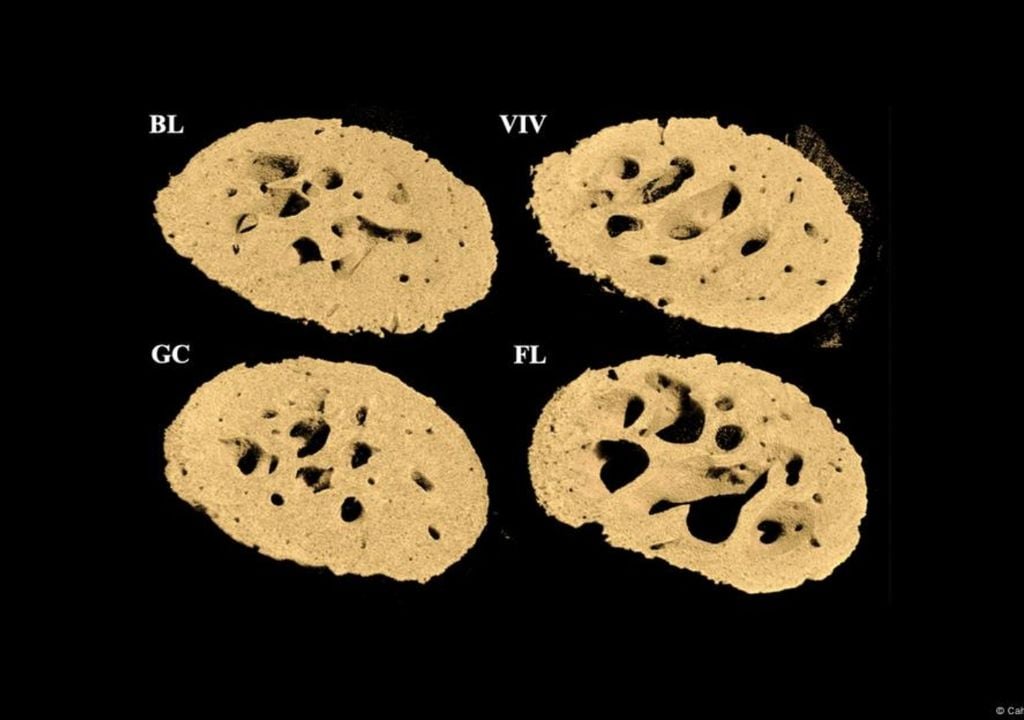

Os resultados surpreenderam os cientistas: ao fim de 37 dias, os ossos dos animais apresentavam alterações estruturais impressionantes. Descobriram que os ossos que normalmente suportam peso — como os fémures — foram os mais afetados.

Após pouco mais de um mês em órbita, os investigadores detetaram uma degradação óssea acentuada nas patas traseiras dos roedores, com grandes cavidades a indicar perda de densidade mineral.

Uns ossos com buracos, outros mais fortes

A deterioração não foi generalizada, o que descartou a radiação cósmica como causa primária. Em vez disso, a microgravidade parece alterar diretamente o equilíbrio do sistema esquelético.

A análise revelou um padrão curioso: enquanto os ossos de suporte sofreram uma deterioração acelerada, estruturas como a coluna lombar e o crânio permaneceram praticamente estáveis. De facto, algumas zonas do rosto e da mandíbula apresentaram um ligeiro aumento de densidade.

“A tomografia computorizada e as análises histológicas de ossos de ratinhos que voaram no espaço na Estação Espacial Internacional durante 37 dias na experiência Rodent Research-1 da NASA mostram uma perda óssea cortical e esponjosa significativa específica a ocorrer no fémur, mas não nas vértebras L2”, refere o artigo, publicado na revista PLOS ONE.